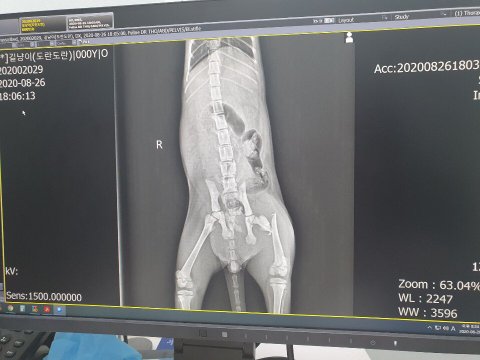

거기서는 의사선생님이 수술해야 한다고 하셨어요. 그런데 수술하기 위해서 먼저 CT-MRI를 촬영해야 하는데 애기 상태가 심각했어요 (의사선생님 말씀대로는 차에 쳤다는 가능성이 100%): 뒷다리 양쪽이 골절인데다 방광이 손상이 되서 출혈의 원인이 됐어요. 그래서 일단 어제까지 수혈을 맞게 해서 내일쯤에 촬영 들어갈 수 있다는 소식이 들어왔어요 ㅠㅠ